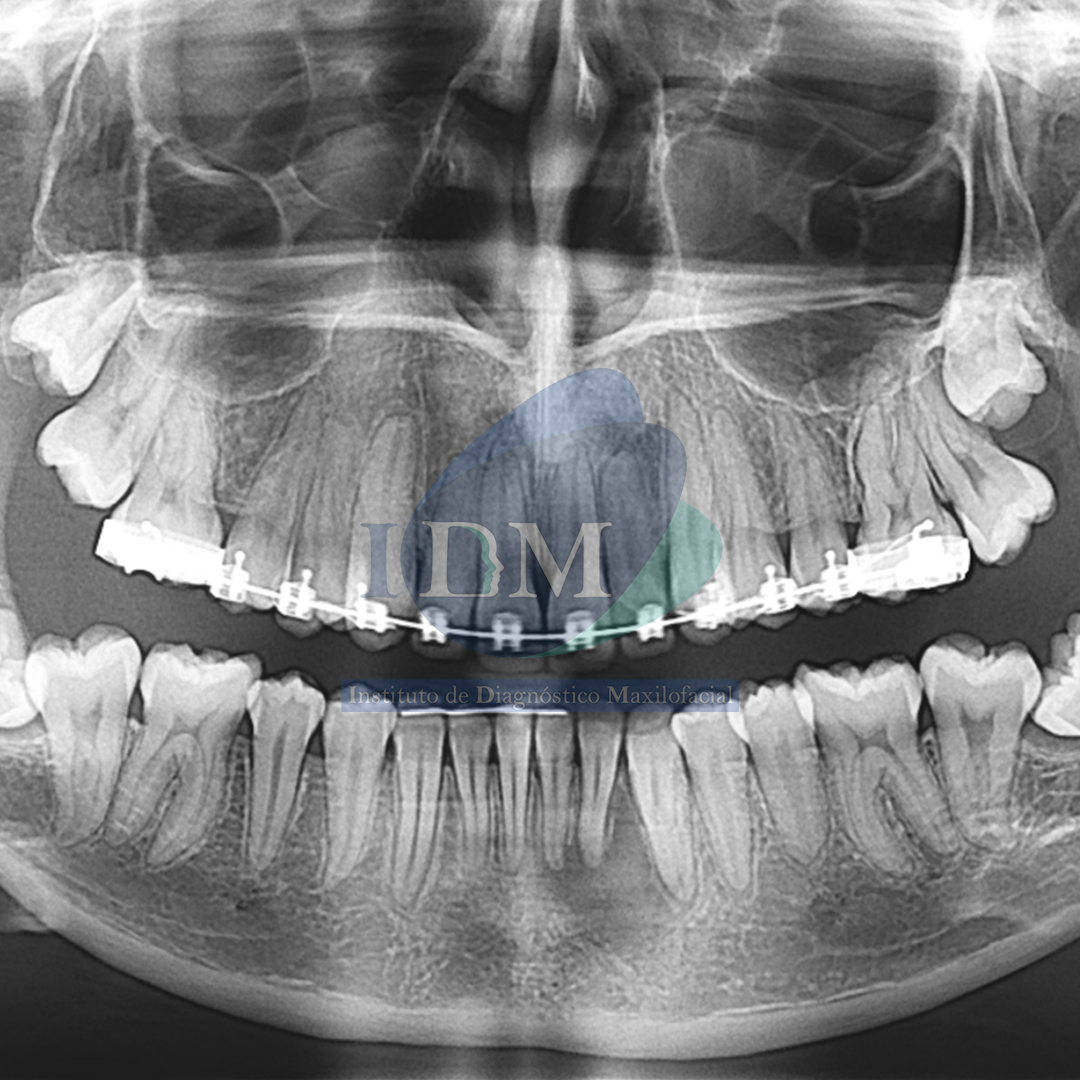

Paciente femenino de 17 años de edad, es referido al Instituto de Diagnóstico Maxilofacial – IDM para evaluación por presentar dolor en zona anteroinferior del maxilar inferior.

En la radiografía panorámica (Figura 1), se aprecia proceso osteolítico periapical en pieza 32.

Radiografia Panorámica

A la evaluación de la tomografía volumétrica (CBCT) en los cortes axiales (Figura 2) y transaxiales (Figura 3), se aprecia proceso osteolítico periapical en pieza 32 que ocasiona el borramiento parcial de la lámina dura de piezas 33 y 31, a la vez se evidencia presencia de dos conductos a nivel de tercio cervical y medio que convergen a nivel apical en piezas 32, 31, 41, 42.